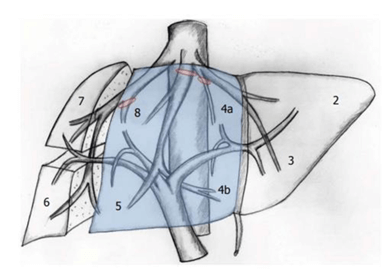

Our patient had a centrally located hepatocellular carcinoma. Centrally located hepatocellular carcinoma is defined as a tumor situated in segment IV, V and VIII according to Couinaud’s segmental anatomy of the liver and adjacent to major vascular structures (Figure 4) [4, 7].

Figure 4: Central hepatectomy according to Couinaud’s liver anatomy [4].

Centrally located hepatocellular carcinoma can be treated by either central hepatectomy or major hepatectomy [9]. Central hepatectomy removes most or the entire segment 4a and 4b and all or most part of the segment 5 and 8 with or without segment 1 [4]. Multiple studies showed good outcomes with central hepatectomy [4, 7, 9-12]. But this technique has its advantages and disadvantages. Central hepatectomy increase the future liver remnant volume, reducing the risk of post-operative liver failure and patient with late-stage recurrence in central hepatectomy are more likely to receive hepatectomy again [9].

There are two main techniques for performing central hepatectomy. The first technique is the ligation and division of the central pedicles supplying segment IV, V and VIII of the liver at the same time of liver parenchyma transection under a pringle maneuver, the second start with extrahepatic individual ligation and division of the vessels supplying segments IV, V and VIII prior to liver parenchyma transection [4]. In this case we used the first technique. We did a ligation of the right portal vein branch supplying the right anterior liver sector (segment V and VIII) and middle hepatic vein supplying segment IVa, IVb, V and VIII during liver parenchyma transection of the liver using hydrojet under pringle maneuver. During this transection we have to be careful to preserve the right posterior branch of the right portal vein supplying segment VI and VII of the liver. And it’s important to preserve the left hepatic portal vein branch supplying segment II and III during ligation of the branch supplying segment IVa and IVb, and to avoid any injuries to the right and left hepatic vein during middle vein ligation leading to ischaemia or necrosis of the residual peripheral liver causing liver failure and increased mortality.